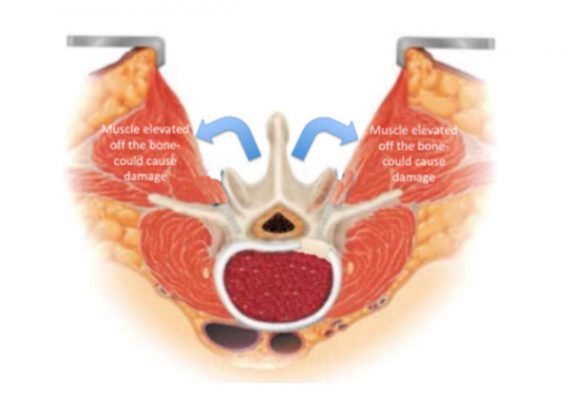

Phẫu thuật cột sống ít xâm lấn (Minimally Invasive Spine Surgery) là các phẫu thuật cột sống sử dụng đường mổ nhỏ và hệ thống ống nong để tiếp cận và sửa chữa các thương tổn bệnh lý của cột sống khác với đường mổ truyền thống.

– Ít tổn thương cơ – xương – phần mềm